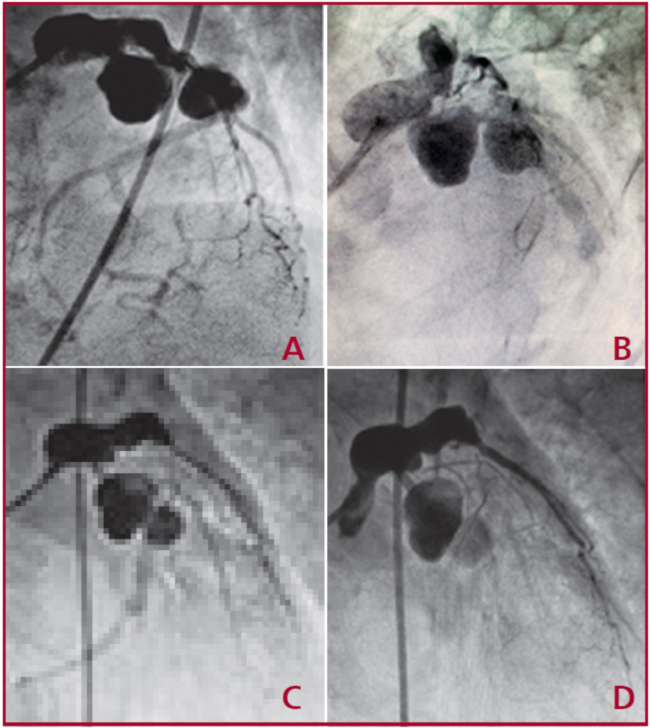

Se decidió su internación en la unidad coronaria con diagnóstico de angina post IAM (APIAM) en plan de cinecoronariografía de urgencia (Figuras A-D), en la cual se visualizaron: aneurisma fusiforme de tronco de coronaria izquierda de 12 a 15 mm, oclusión proximal de la arteria descendente anterior, aneurisma fusiforme proximal de la arteria descendente anterior y aneurismas saculares grandes en tándem, proximales de la arteria circunfleja.